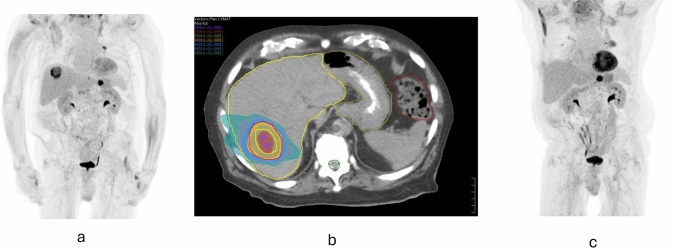

Abstract Image